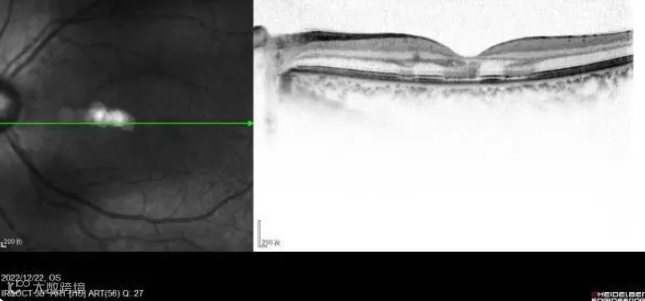

1月9日,媒体从该院了解到,女子在感染新冠后突然视力下降,看不清东西,被家人送至医院检查。经眼部专科检查,她的双眼黄斑区可见暗红褐色病灶,色素紊乱,外层视网膜高反射病灶,集中在黄斑区视网膜外核层,椭圆体带和嵌合体带断裂。结合病史及专科检查,医生确诊其为急性黄斑区神经视网膜病变。